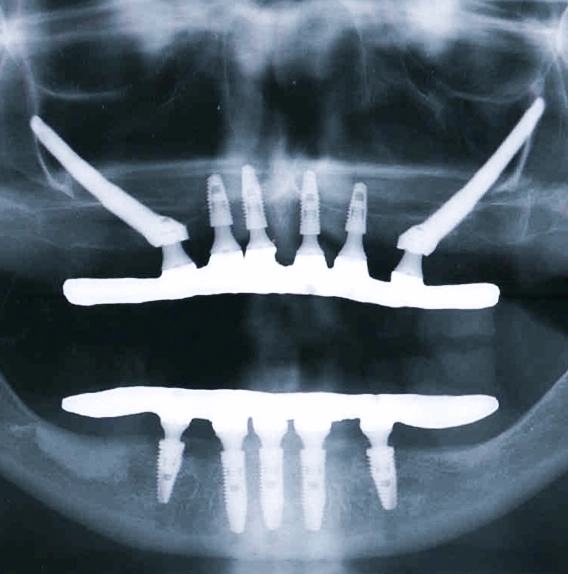

Implantes zigomáticos:

Solução para casos de perda óssea severa.

Em situações em que há grande reabsorção óssea na maxila, os implantes convencionais podem não ser suficientes. Nesses casos, os implantes zigomáticos são uma alternativa segura e eficaz.

Eles são ancorados no osso zigomático (maçã do rosto), dispensando enxertos extensos e permitindo reabilitação oral mesmo em casos considerados complexos.

Com mais de 12.000 implantes dentários realizados e atuação com implantes zigomáticos desde 2006, o Dr. Gustavo Terra conduz os tratamentos com planejamento preciso, tecnologia avançada e foco absoluto na previsibilidade dos resultados.